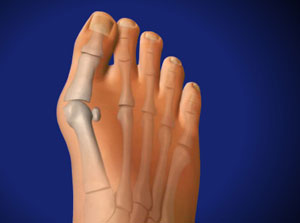

El hallux valgus es la desviación de la punta del dedo gordo hacia afuera y de la cabeza del primer metatarsiano hacia adentro, formando un ángulo abierto hacia afuera.

El juanete es la prominencia de la cabeza del primer metatarsiano a consecuencia de diversas causas, tales como higroma, osteofito, quiste sinovial, metatarso varo, etc. Suele acompañar al hallux valgus, pero también se puede presentar aislado.

La prominencia medial de la cabeza del primer metatarsiano aparece cuando el ángulo entre el primer y el segundo radio supera los 10° con más de 18° de hallux valgus.

La manifestación más evidente de la deformidad es la prominencia de la cabeza del primer metatarsiano.

- Aumento de la anchura del antepié, con la diáfisis del primer metatarsiano separándose hacia dentro del segundo.

- El metatarsiano aparece corto, desviado en varo con un ángulo mayor de 15º y puede tener cierto grado de pronación. La cabeza del metatarsiano desarrolla una bolsa protectora (juanete) donde roza con el zapato; puede presentar exostosis y osteofitos.

- La falange proximal del dedo gordo se inclina lateralmente hacia el segundo dedo, el cual está apiñado y puede llegar a deformarse.

- La articulación metatarsofalángica está subluxada, con distensión de los ligamentos externos y acortamiento de los internos. Puede haber artrosis.

- Desviación de los sesamoideos al espacio intermetatarsiano, con desplazamiento del tendón largo del dedo gordo. Esto suprime el principal apoyo del antepié, altera la acción muscular e impide la corrección en varo del primer metatarsiano.